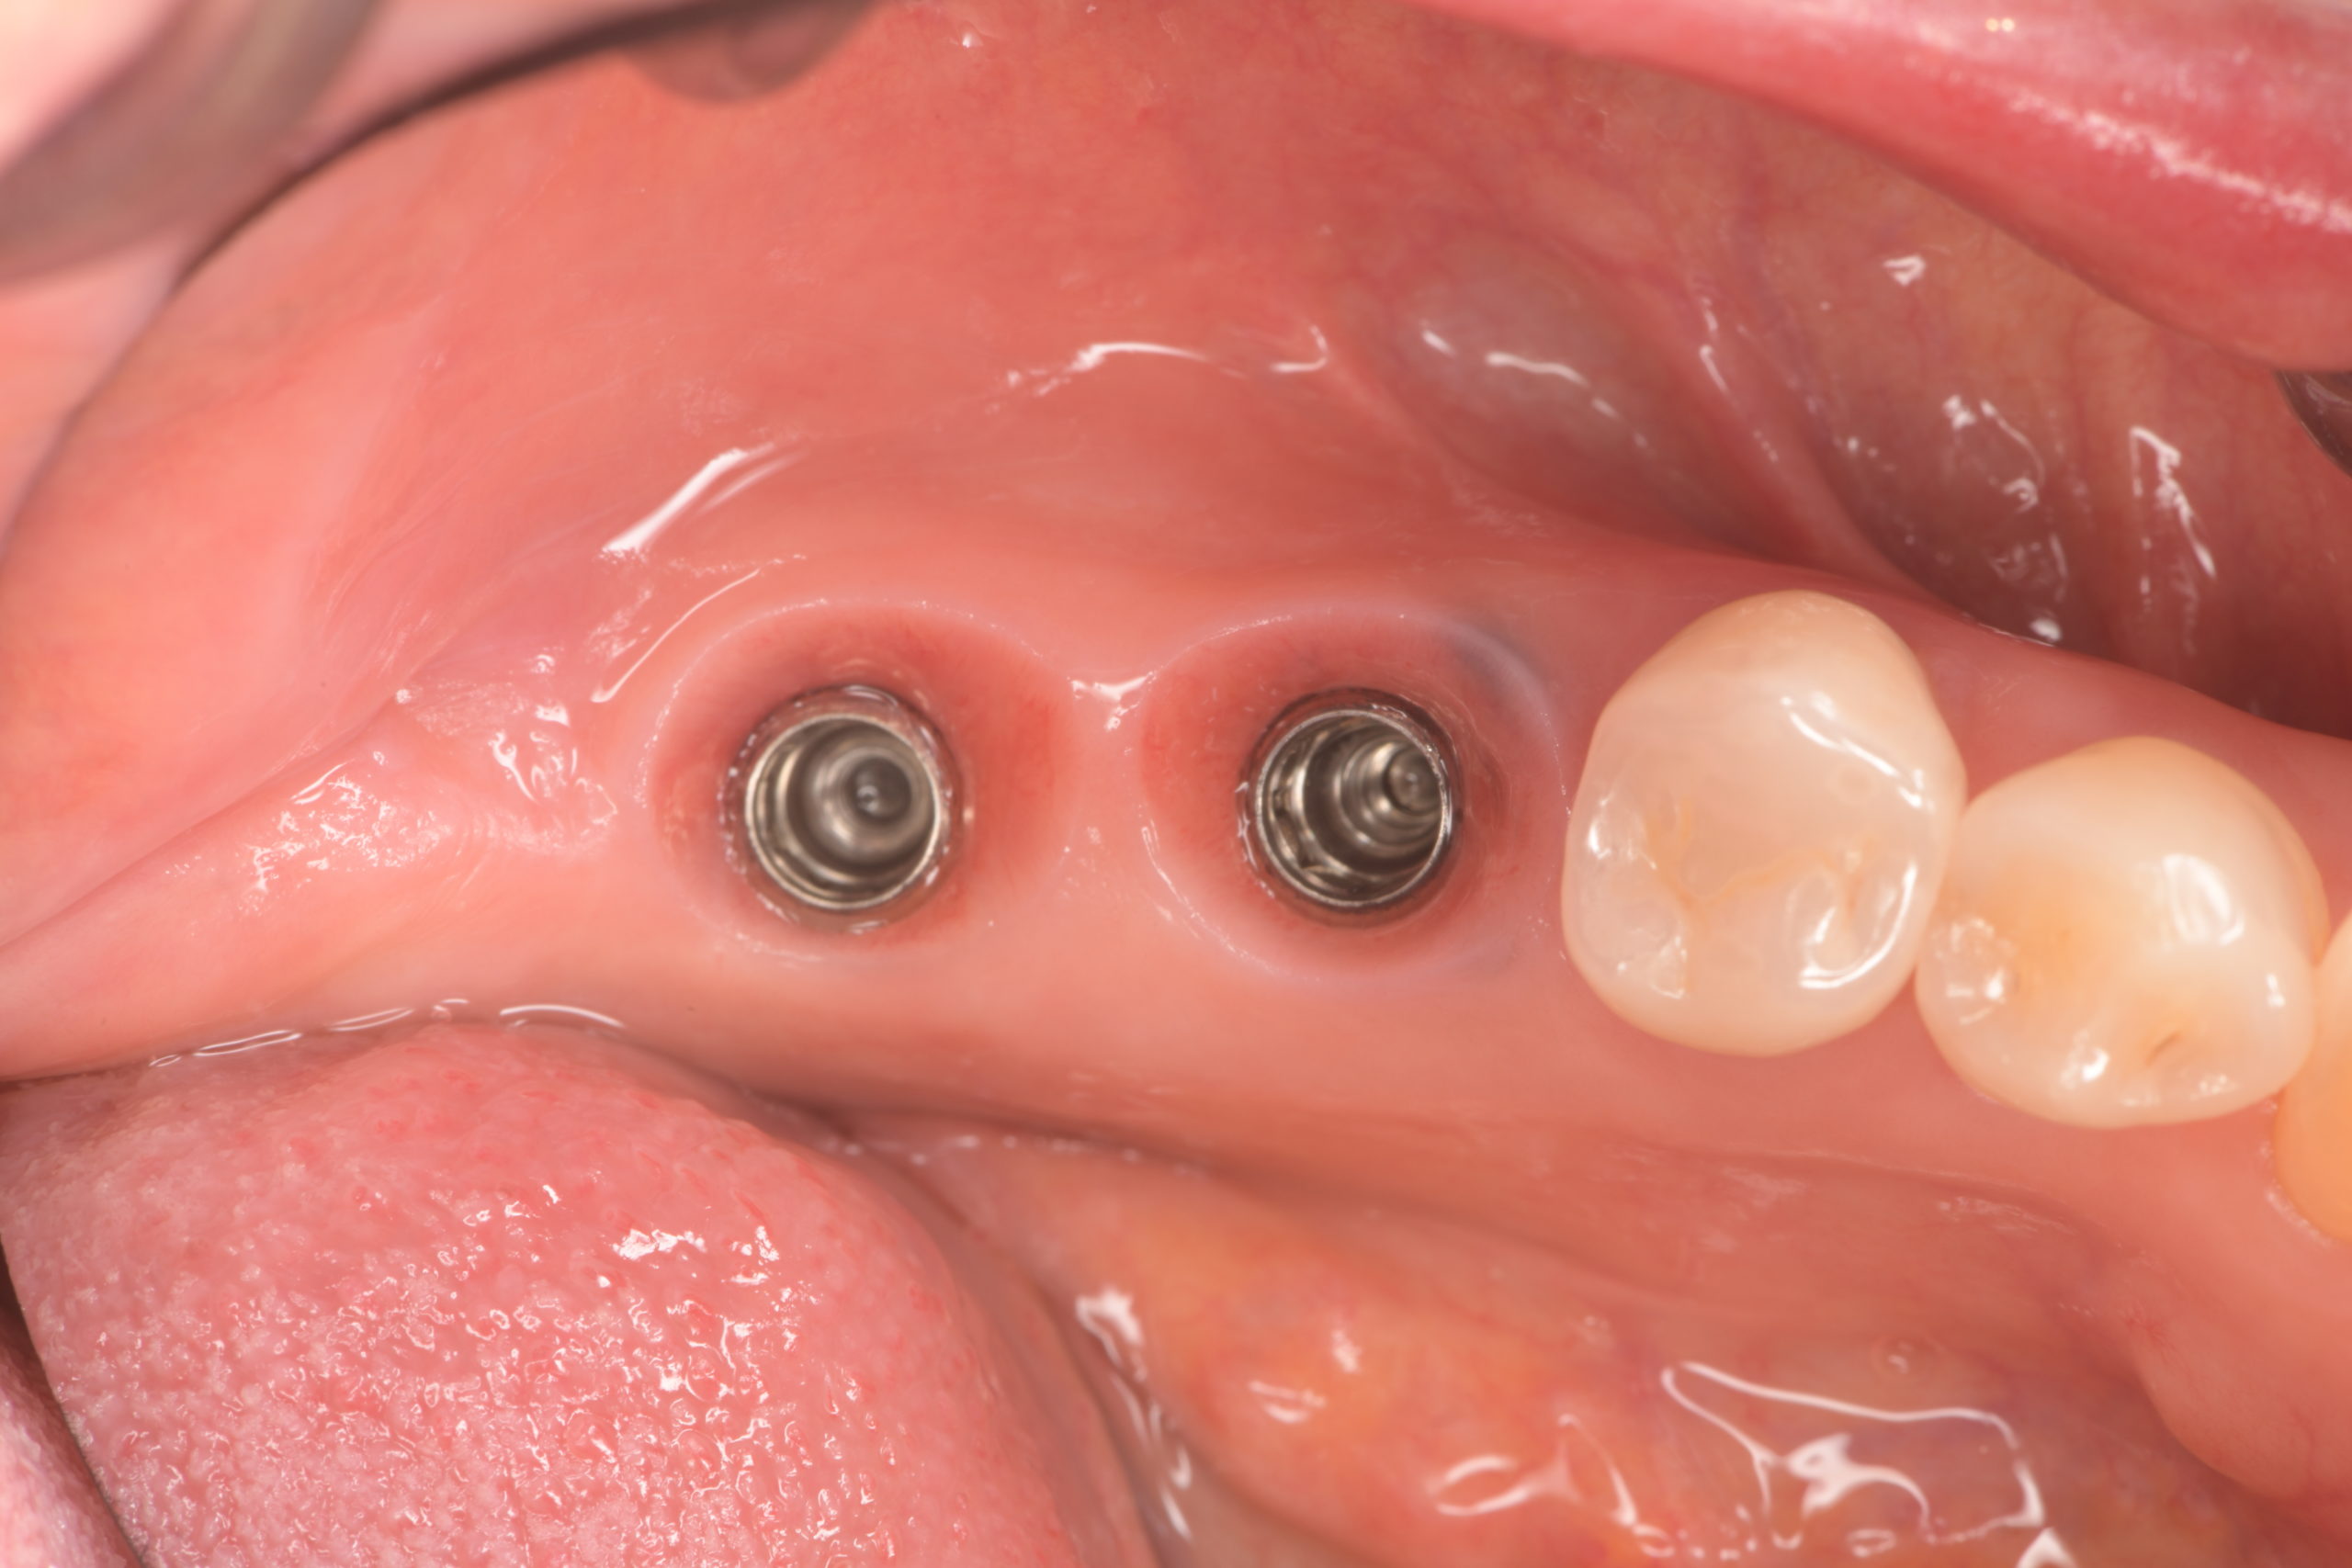

下顎臼歯部インプラント治療前

下顎臼歯部インプラント上部構造装着前

下顎インプラント治療完了